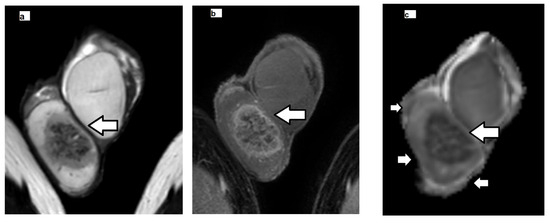

2.3. MRI Data Postprocessing